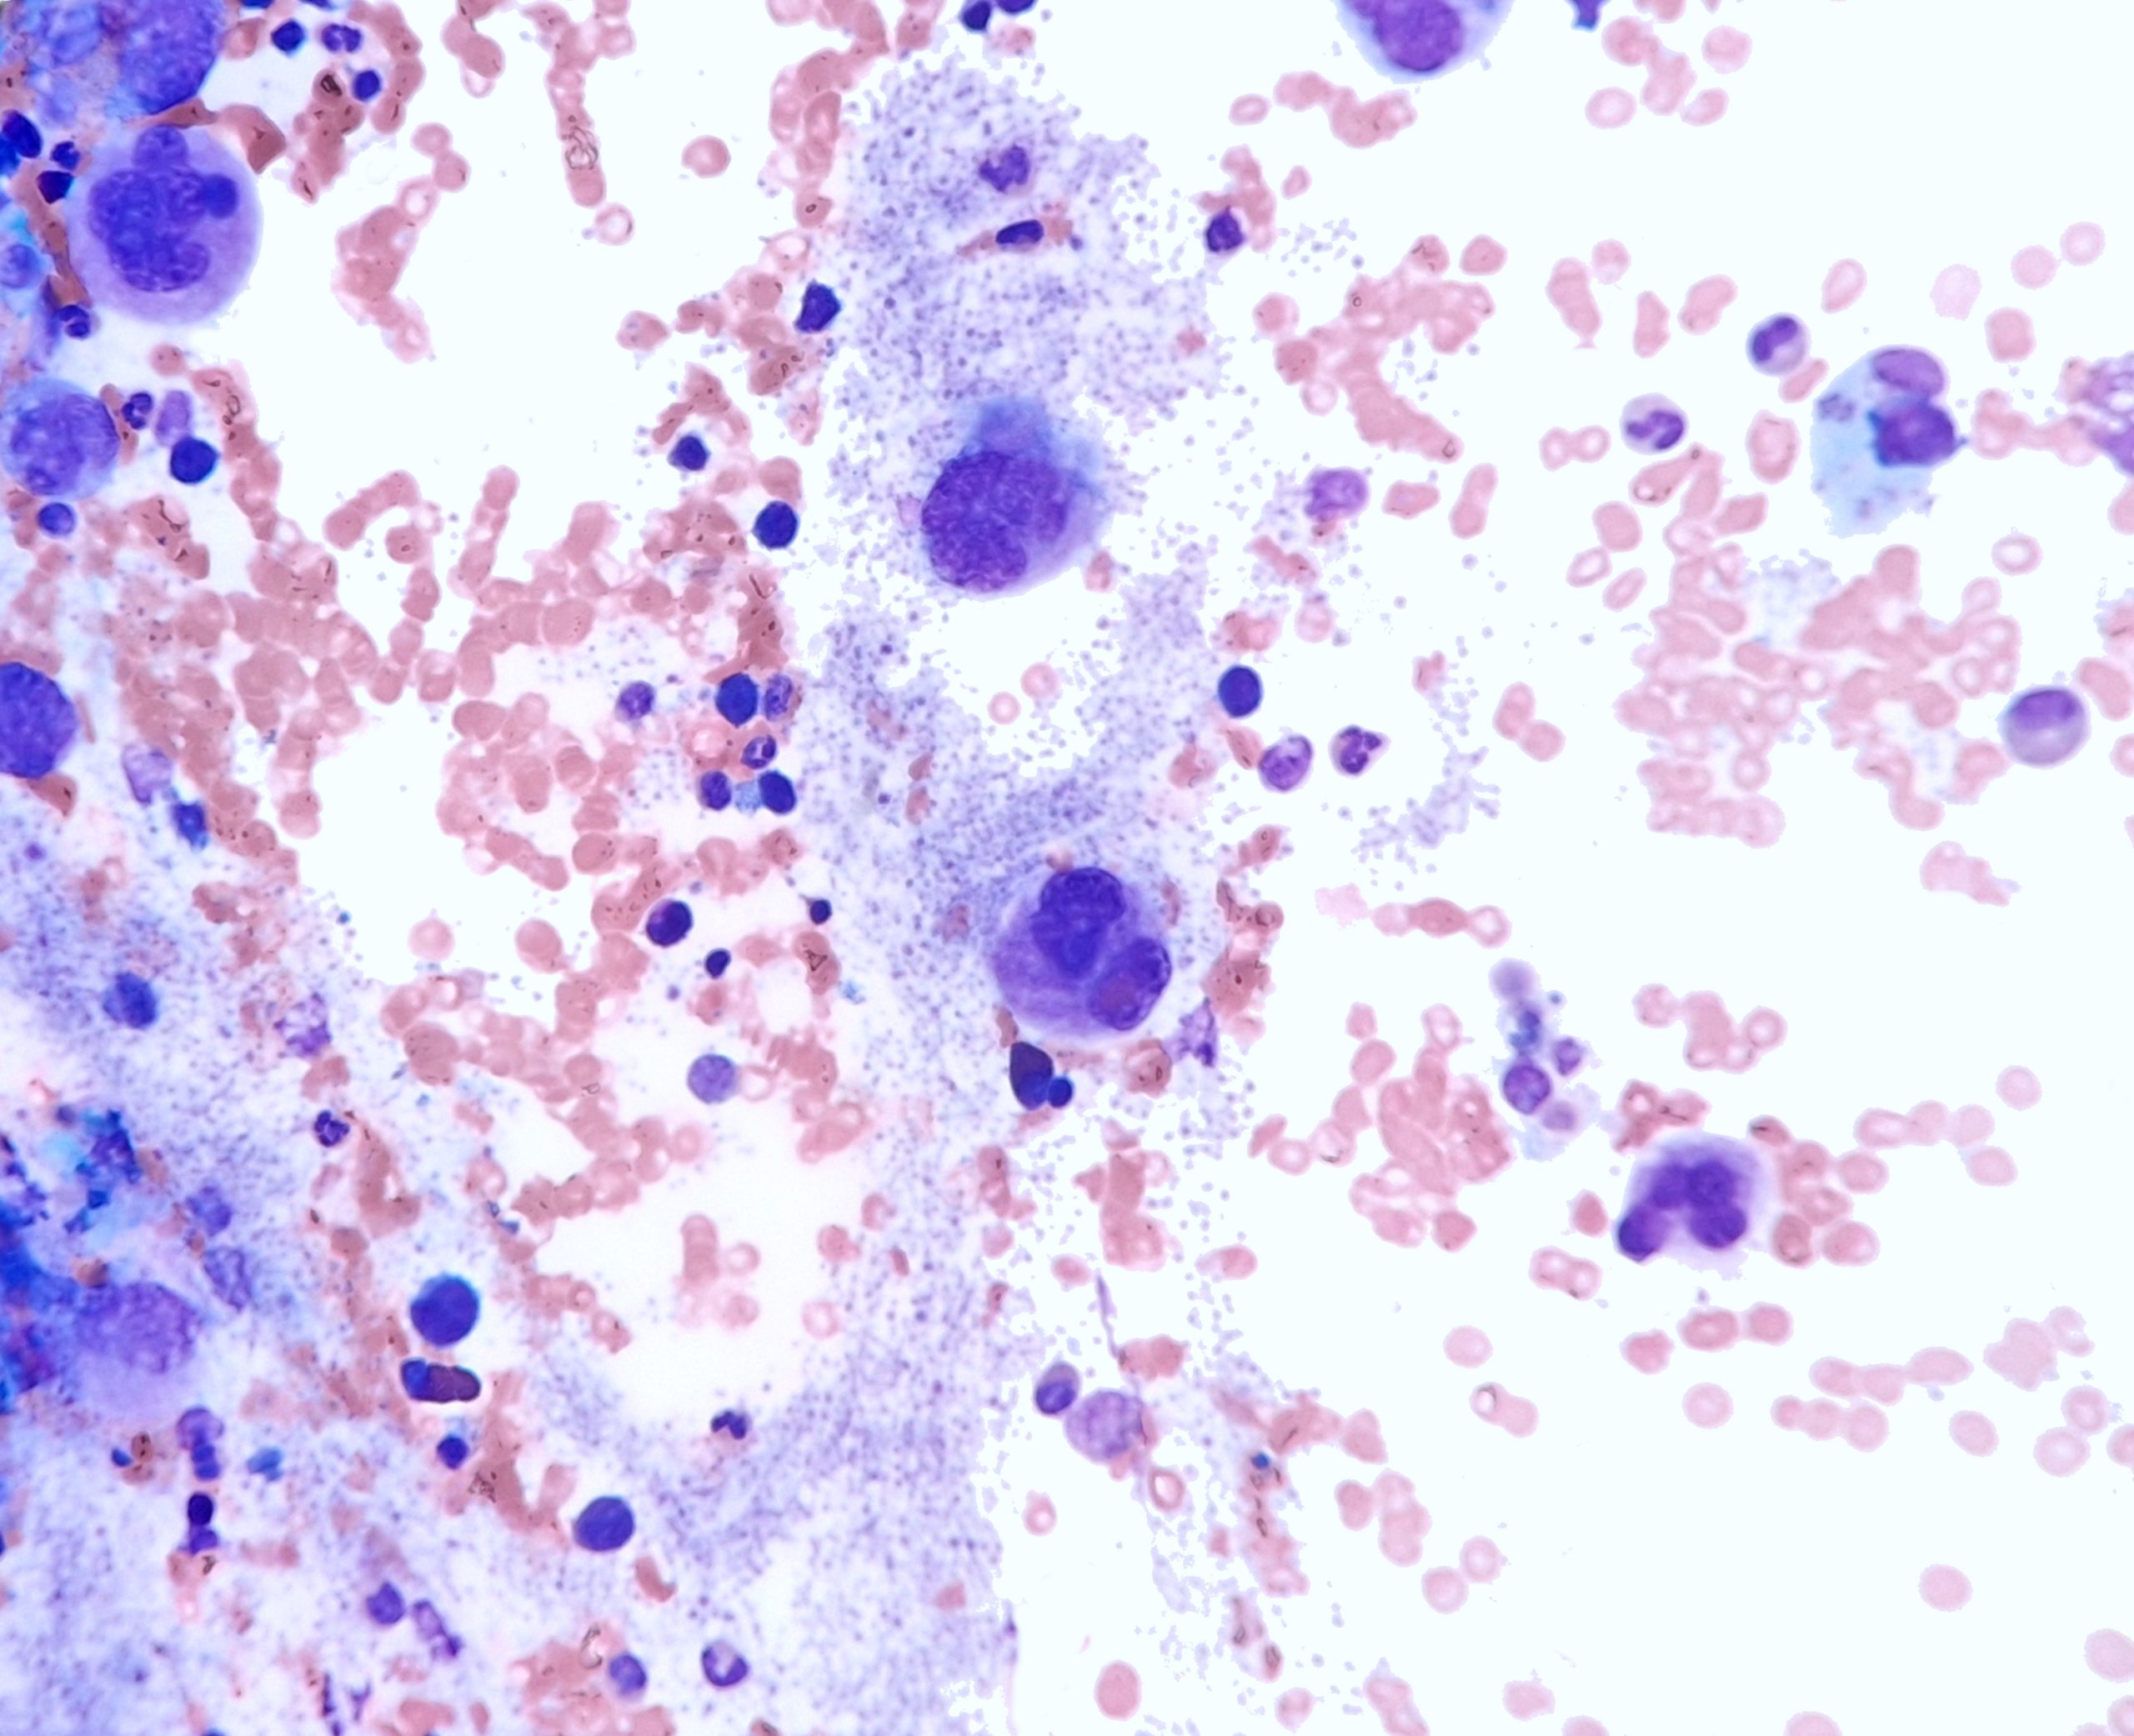

Case Presentation: This case highlights a 31-year-old female who presented with severe post-prandial abdominal pain and night sweats who was identified to have marked thrombocytosis (2.5million) with only a mild leukocytosis(20K). The patient was admitted to the hospital for urgent evaluation given the risk of untreated extreme thrombocytosis. A bone marrow biopsy was conducted which demonstrated micro megakaryocytes, characteristic of CML(Chronic Myelogenous Leukemia). Her blood was positive for the BCR-ABL fusion protein, and she was diagnosed with CML. During admission, the patient experienced an under-appreciated complication of extreme thrombocytosis – prolonged bleeding from her biopsy site due to acquired Von Willebrand deficiency. After resolution, the patient was started on Dasatanib daily therapy and her blood counts readily started to improve. Her abdominal pain resolved once platelet levels lowered with therapy.